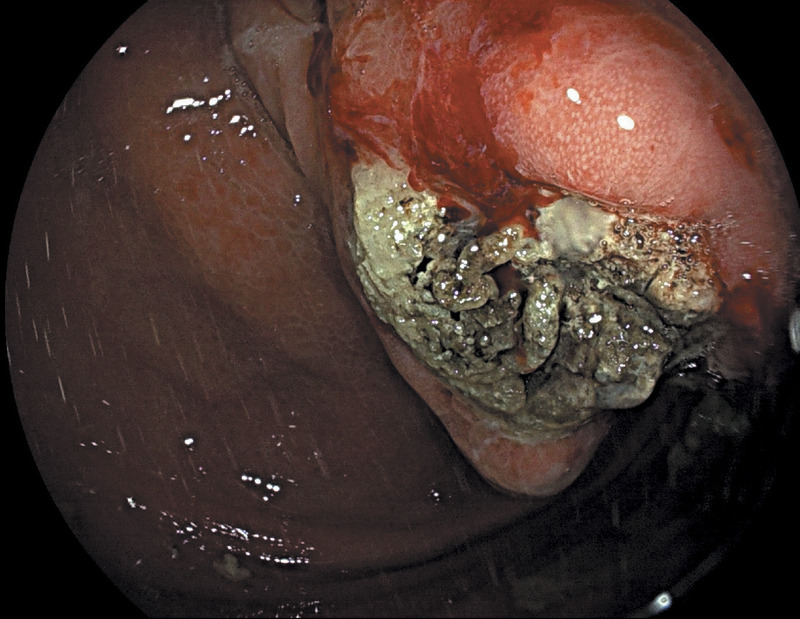

EUS-guided cyanoacrylate glue injection for the management of refractory bleeding from postglue ulcer following gastric varices treatment (with video).